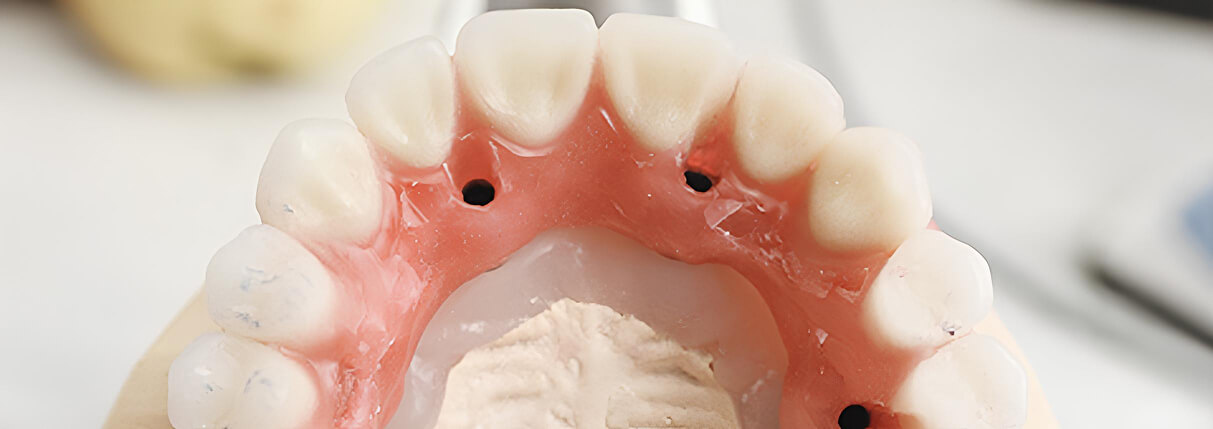

3. Встановлення формувача ясен

Тривалість: 10-15 днів. Після успішного приживлення імплантату встановлюється формувач ясен – невеликий елемент, який допомагає підготувати м’які тканини для майбутньої коронки.

Сканер передає положення імпланта в кістці і по відношенню до сусідніх зубів, і інформацію передають у лабораторію. Процедура швидка, але точність її виконання вкрай важлива.

5. Протезування

Тривалість: до 2 тижнів.

На фінальному етапі виготовляється і встановлюється коронка – зовнішня частина зуба. Хоча процес виготовлення коронки займає деякий час, встановлення виконується швидко і безболісно.